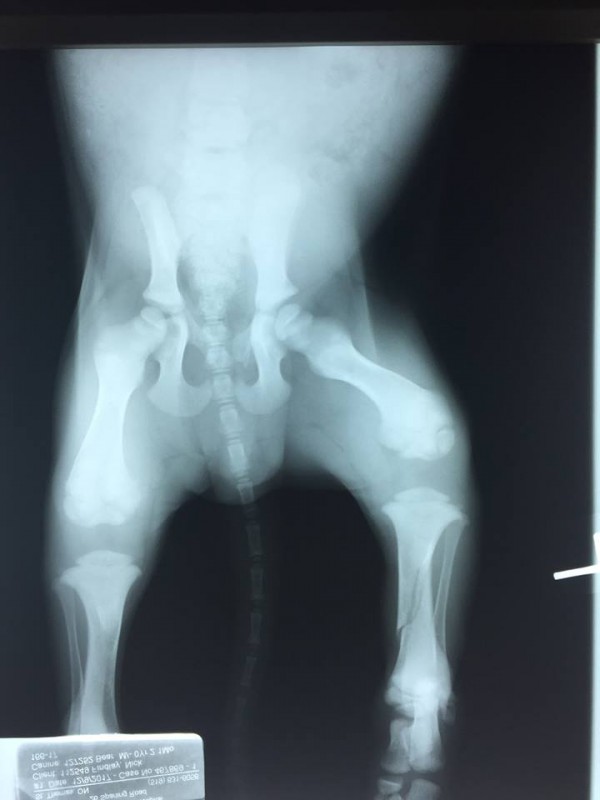

X-Rays of broken back left leg taken December 9th, 2017 prior to surrender this week to BHRR. Tibia & Fibula affected

A Vet Hospital highly recommended our Rescue Program for this wee dude has a broken back leg – Tibia & Fibula.

His leg was broken December 8th so time is of the absolute urgency.

You see he has a broken leg – broke over a week ago – tibia & fibula and needs our immediate assistance…

BHRR was founded as a Great Dane/Giant Breed Rescue that focuses strongly on the special needs and this wee pup needs medical attention/surgery immediately in order for us to have the best chance of saving that leg. If it is not possible to save the leg, it will be amputated and like all of our fabu tripods, he will go on to live an amazing painfree quality filled life.

Repeat x-rays were done and due to the original splint, the alignment of his bones were not perfectly straight and as a result, he has some ‘bowing’ in that leg. There is clear calcification going on as the bones are healing and he may always have some permanent bowing in that leg.

X-rays are now sent off to Dr. Philibert, the ortho specialist to review.